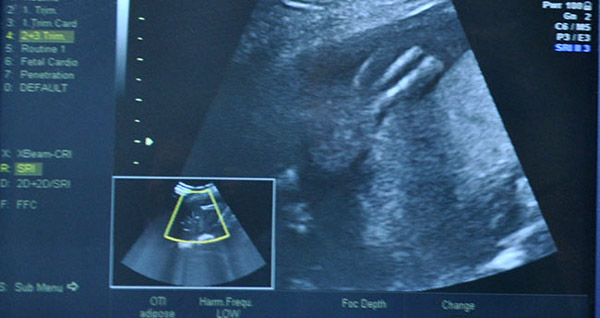

Amniyotik band sendromu nedeniyle ayağı gelişmeyen 300 gr.lık bebeğe anne karnında ameliyat gerçekleştirilerek bebeğin ayağını kaybetme ihtimali ortadan kaldırıldı.

Konya'da gebelikte nadir görülen "Amniyotik band sendromu" sebebiyle ayaksız doğma ihtimali olan 300 gr ağırlığındaki bebeğe anne karnında müdahale edildi. Konya'dan hastaneye başvuran 5 aylık hamile Hanife Altan'ın bebeğine amniyotik band senromu teşhisi konuldu. Bebeğin içerisinde bulunduğu amniyot sıvının bulunduğu zarın parçasının ayrılarak bebeğin sol ayağını sarması üzerine bebeğin ayağının tamamen kaybolma ihtimalinin ortaya çıktığı belirtildi.

Nadir olarak rastlanan amniyotik band sendromu sonrasında bebeğin ayağında kan akışınınsağlanamasından dolayı ayakta gelişim geriliğinin olduğu belirlendi. Söz konusu durum karşısında tamamen ayağını kaybetme ve ayaksız doğma riski bulunan bebek doktorların anne karnında yapmış oldukları müdahale sonrasında ayaksız doğma ihtimalinden kurutuldu.   Bakmanızda Fayda Var: Amniyotik Band Sendromu Nedir?   ayağı gelişmeyen bebeğe ameliyat

Daha 300 gramlık olan bebeğin ayaksız doğmaması için uzman doktorlar riskli bir operasyonu başarıyla gerçekleştirdiler. Ameliyat sonrasında sağlık durumu iyi olduğu açıklanan ve doğuma kadar düzenli olarak takip edilecek olan bebeğin ayaksız doğmasının önüne geçilmesi herkes tarafından mutluluk kaynağı oldu.   ayağı gelişmeyen bebek